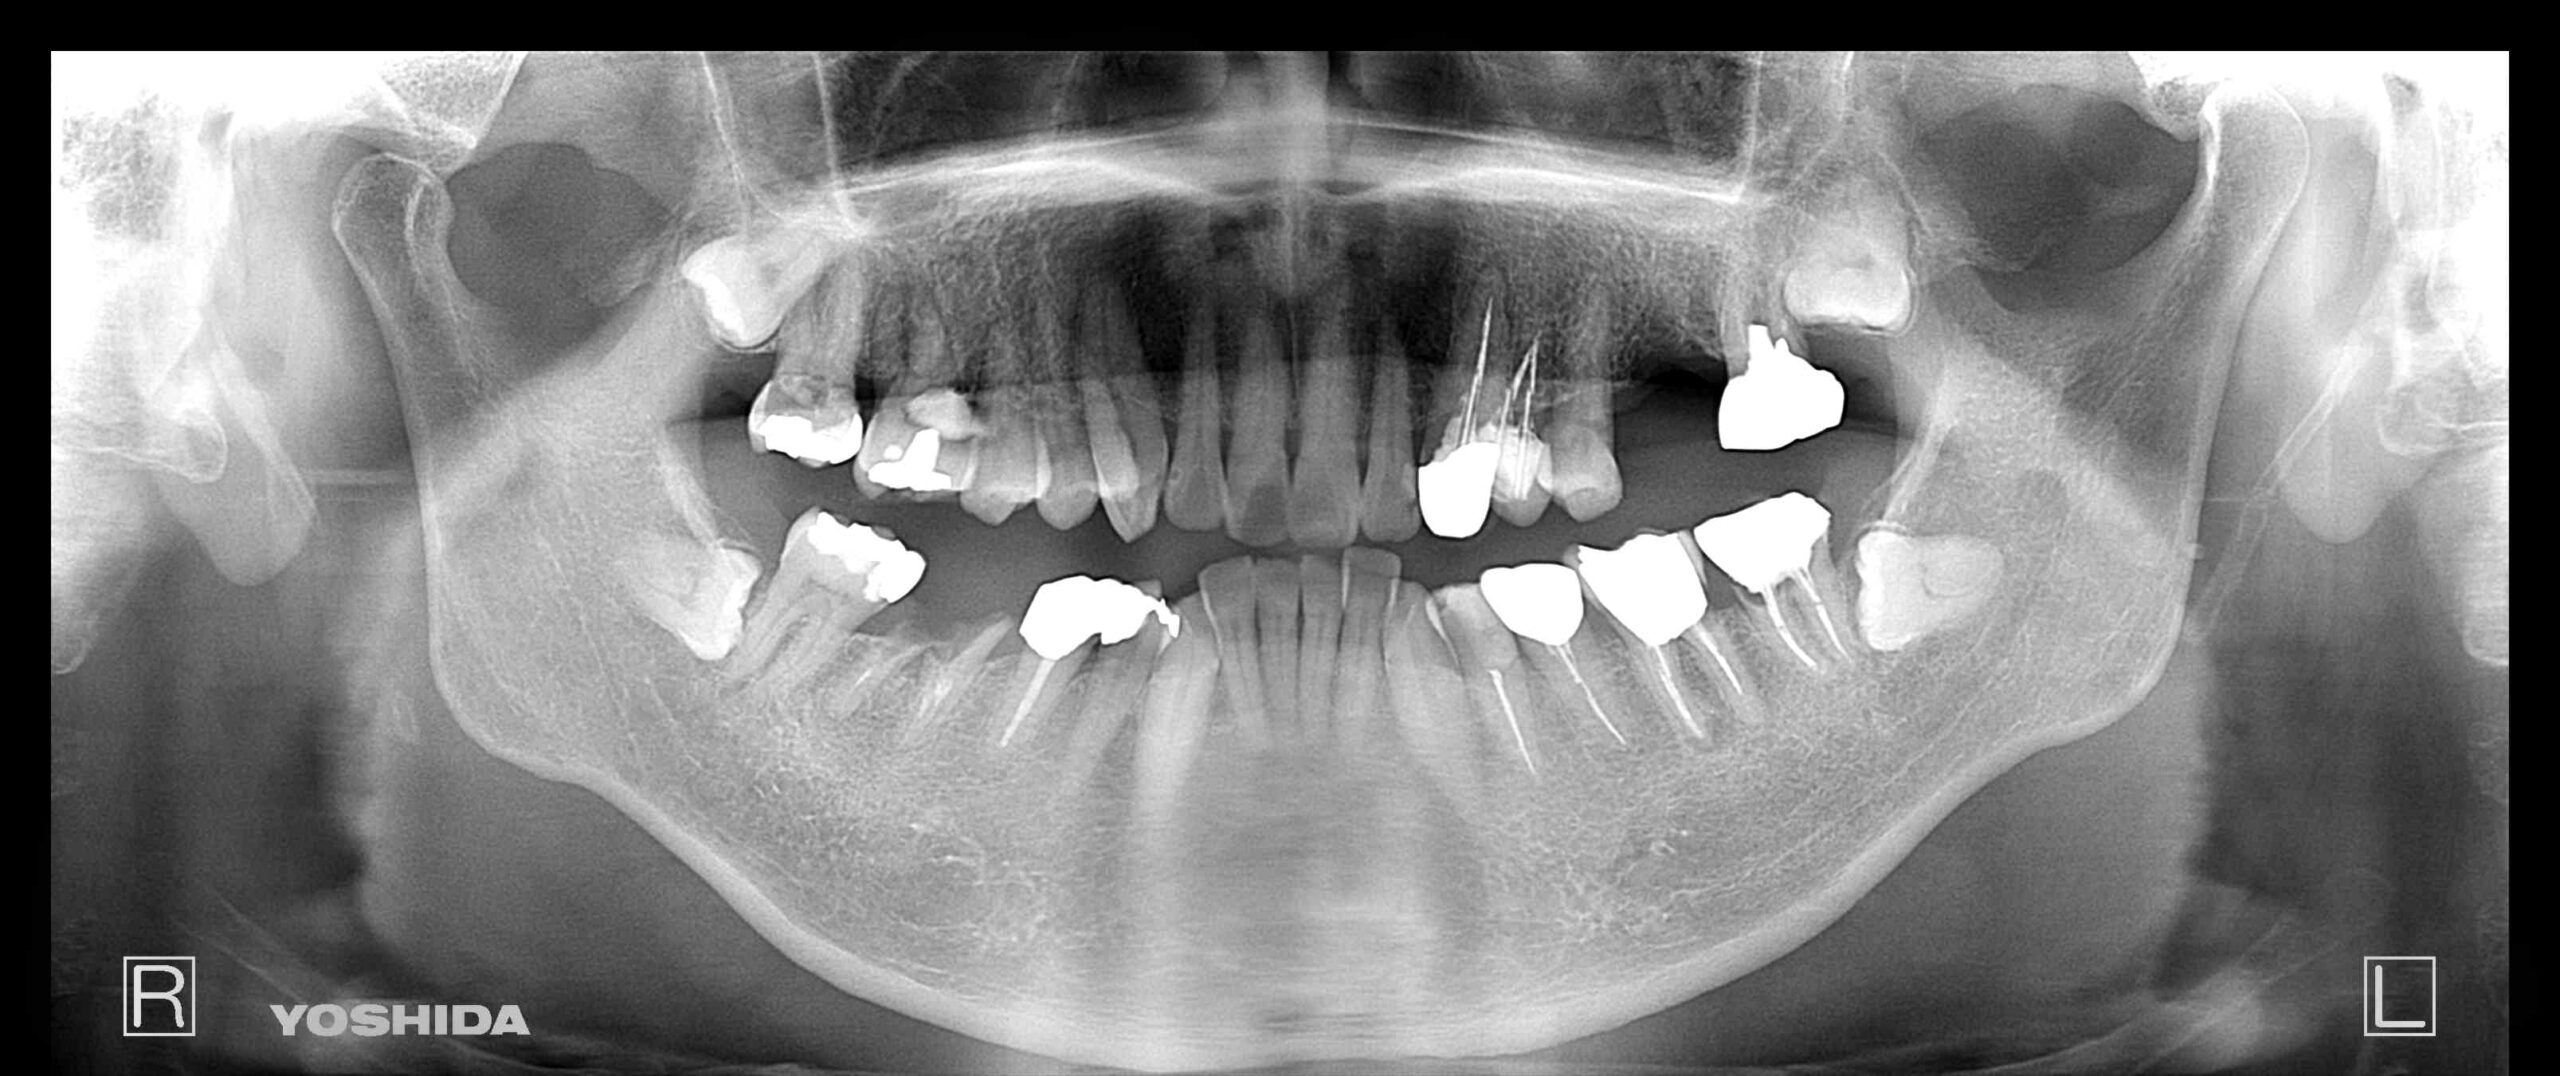

| 主訴 | 欠損部の補綴にインプラントを希望 |

|---|---|

| 年齢・性別 | 65歳 男性 |

| 治療期間・回数 | 8か月 11回 |

| 費用 | 骨造成 30,000 インプラント 300,000×2 |